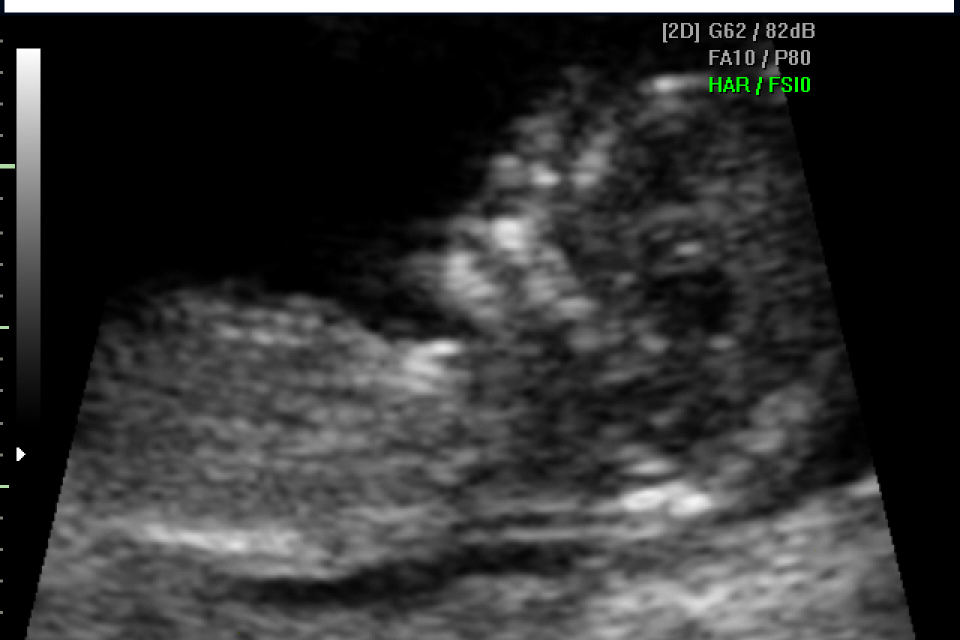

Gia` a queste settimane e` possibile evidenziare la presenza di malformazioni fetali. Inoltre la misurazione della traslucenza retronucale fornisce informazioni sul rischio di alcune anomalie cromosomiche, patologie malformative e anomalie cardiache.

Nella stessa seduta si valuta la crescita fetale, la posizione della placenta e il liquido amniotico. Si puo` misurare la lunghezza del collo uterino parametro importante per calcolare il rischio di parto prematuro